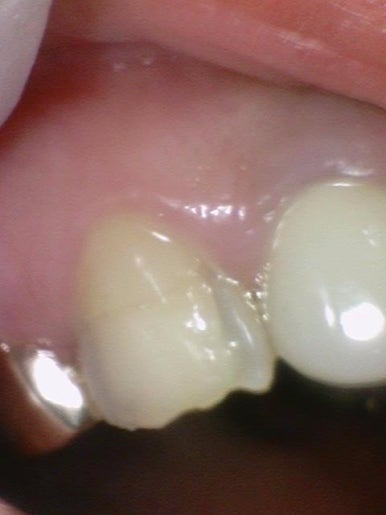

치료 전 처음 내원시 사진

환자분은 치아들이 부식되어 노랗게 보이고 약해져있다며

라미네이트 상담을 하기위해 오신 분이었습니다.

앞니3개에는 오래 전에 한 크라운이 되어있는 상태였는데

모양과 색이 맘에 들지 않는 상태였습니다.

뿐만 아니라 치아들이 단단한 겉면인 건강한 상태가 아니라

단단하지 않고 상아질이 많이 보이는 부식된 상태였습니다.

이의 표면이 녹은 상태 등으로 볼 수 있고,

섭식장애나 구토 등이 있는 사람들에게서 보기 쉽습니다.

정상적이거나 일반적이지는 않은 치아 상태입니다.